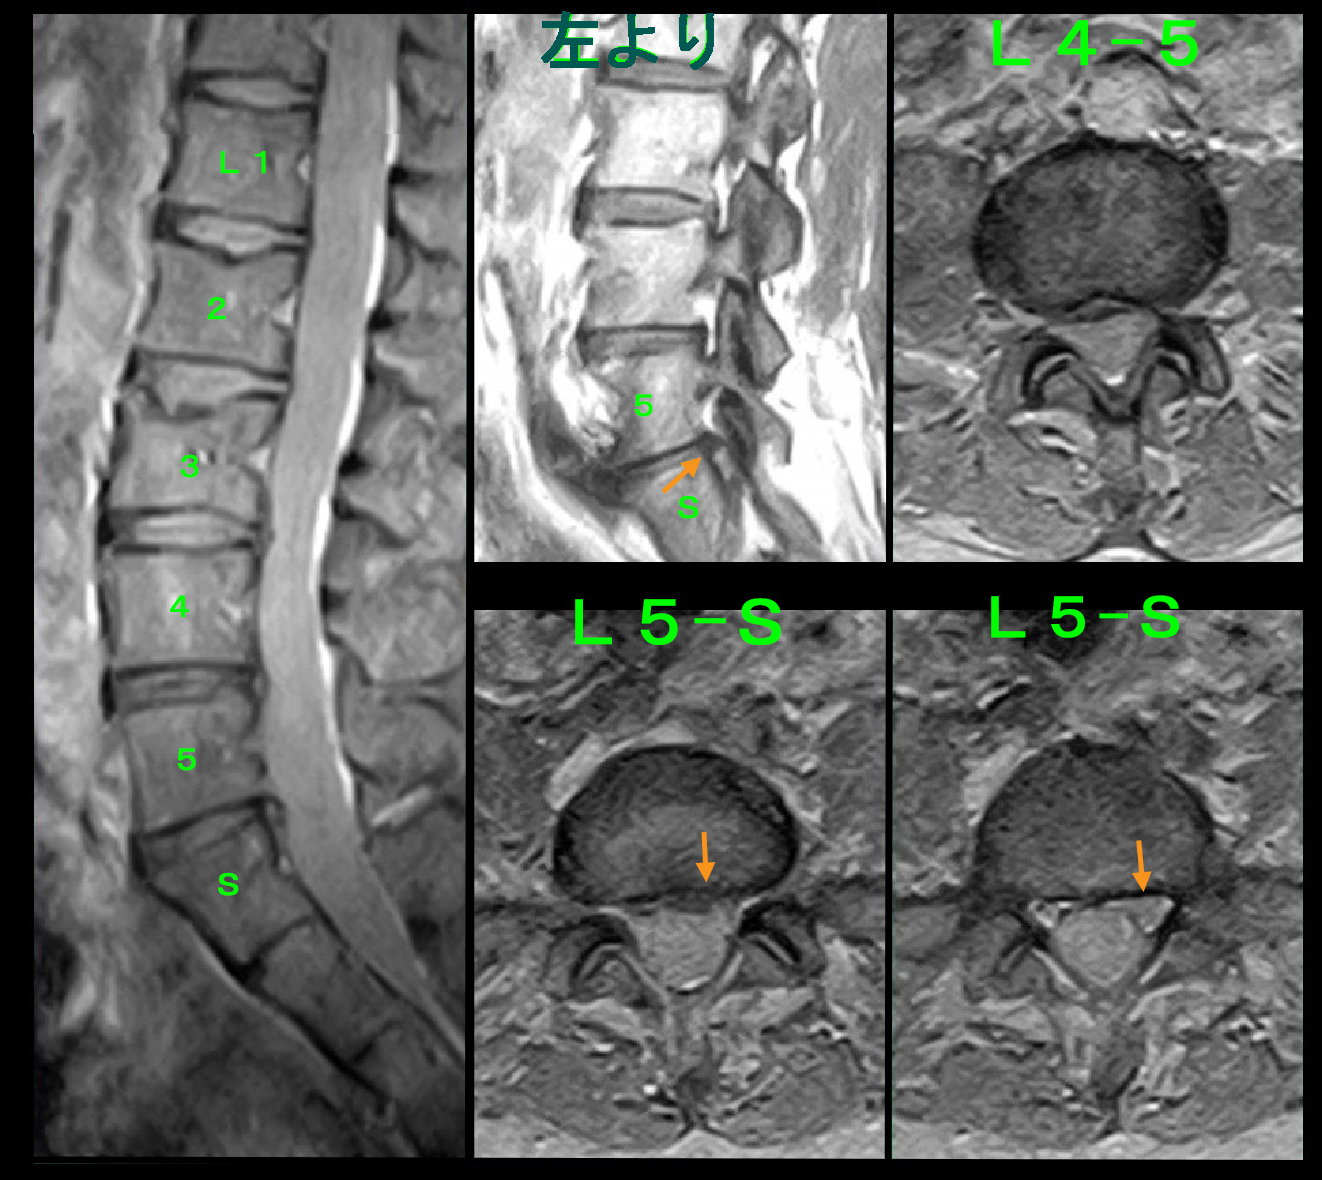

54才女 MR2.jpg

Yさんの痛みの原因はL34ではありませんでした。ならばどの椎間板なのかをMRI所見からみつけださなければなりません。するとT1の矢状断でL5Sの左側で他の椎間板高位より突出が認められ(オレンジ矢印)、4分割の下の2つの画像では左側で軽度の脊髄圧迫、右側では脊髄の外側に中等度のヘルニアがあるようにもみれると評価し、これが病因であろうと判断しました。左S1神経根ブロックを行い、1週間後に再診予定としました。